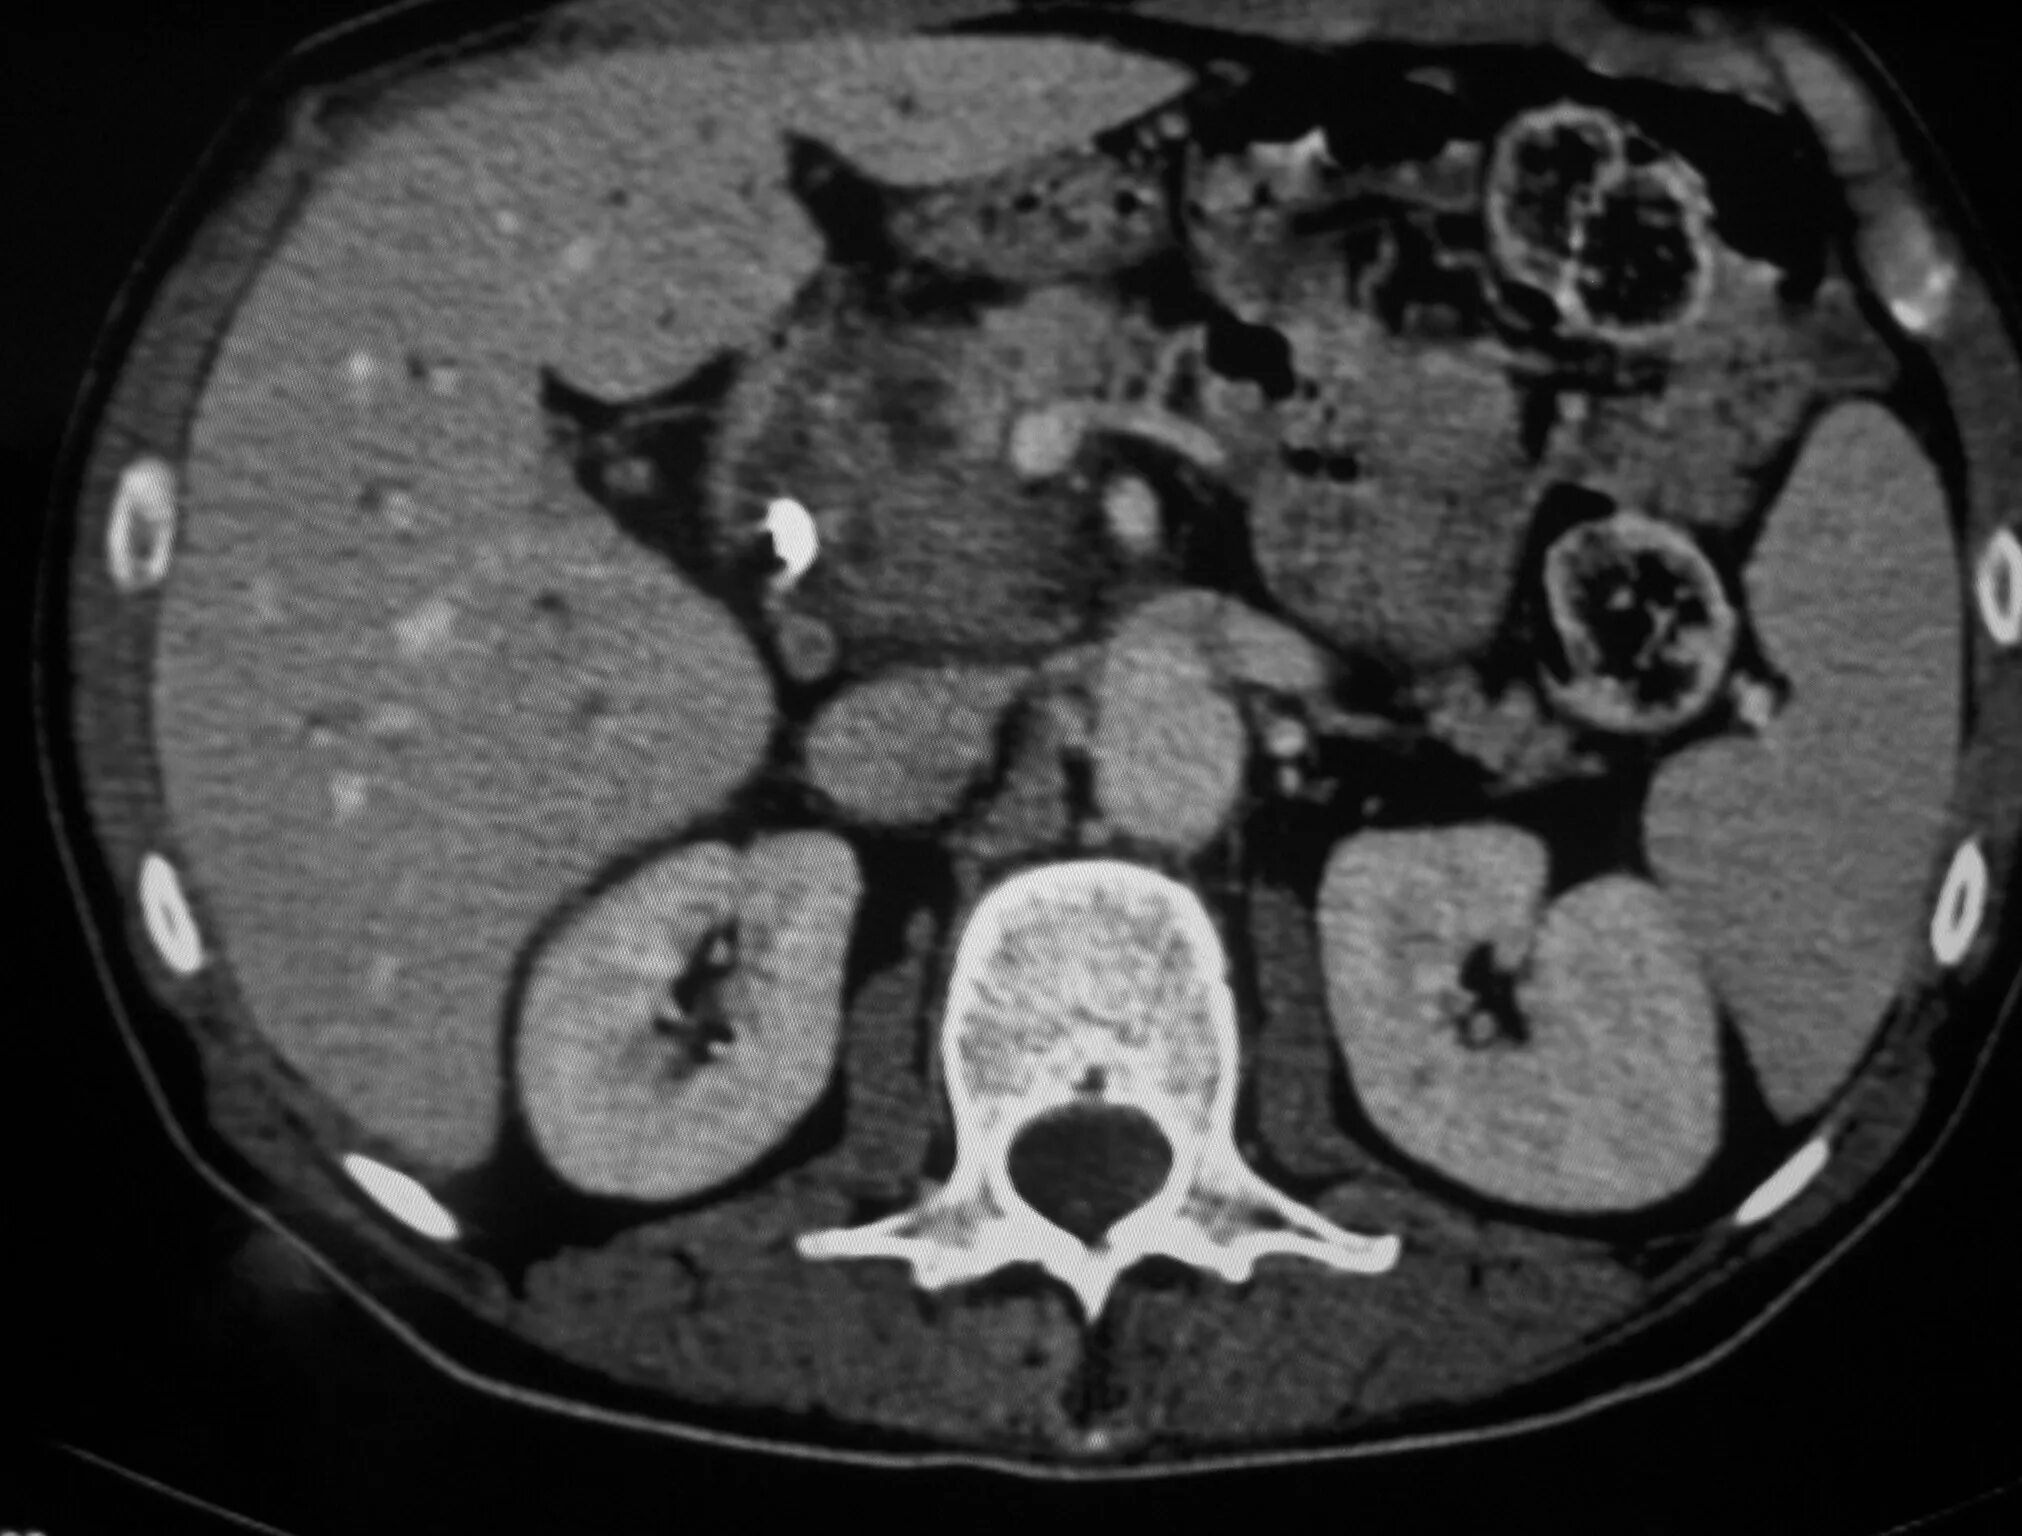

Мрт кисты поджелудочной